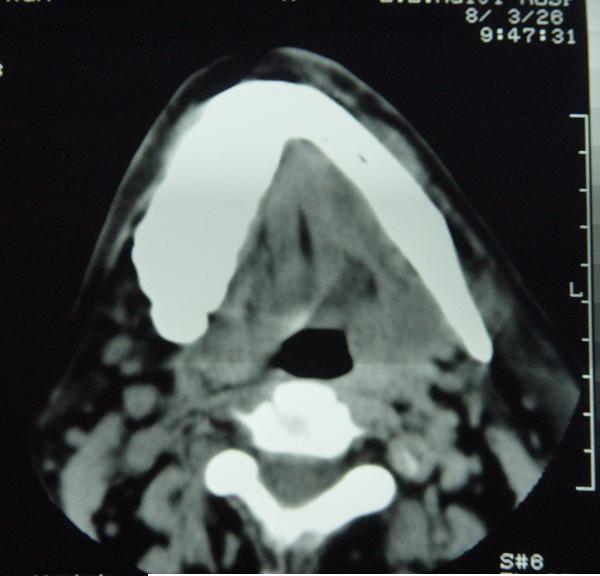

标题: CT12465:下颌骨肿瘤,请会诊 [打印本页]

标题: CT12465:下颌骨肿瘤,请会诊

发现下颌骨肿瘤近30年.逐渐增大.

考虑右侧下颌骨水平部及升部骨纤维异常增殖症可能性大。

考虑右侧下颌骨骨化性纤维瘤。